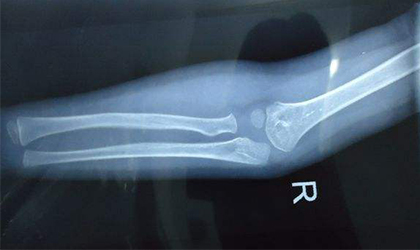

骨折是指骨结构的连续性完全或部分断裂。多见于儿童及老年人,但随着意外事故的多发,骨折的人群也越来越大。“骨折后如何快速康复”是患者关心的重中之重,那么究竟骨折术后怎么才能更快地康复呢?

骨折后怎样恢复得快?康复锻炼不可少!

常州阳光康复医院专家指出前期的正规治疗是骨折愈合的基础,而后期的康复锻炼则是骨折快速恢复的保障。因为合理的运动锻炼,不但能促进局部血液循环,加速新骨的形成,而且能够保障肢体功能的恢复,从而缩短骨折恢复进程。但需要注意的是,骨折后期锻炼不可盲目进行,需在专业医师的指导下分阶段进行。>>>>骨折术后能做哪些训练 我适合吗?